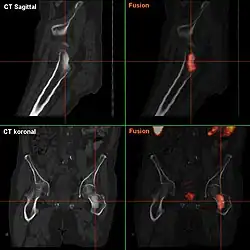

Ausgedehnte Karzinome der Stadien T3/T4 können die Samenblasen, die Harnblase, den Beckenboden oder das Rektum infiltrieren. Die Metastasierung ist zunächst lymphogen (über die Lymphbahnen) in die ortständigen Lymphknoten. Häufig erfolgt später eine hämatogene Aussaat (über die Blutbahn). Typisch sind Knochenmetastasen in Becken, Kreuzbein und Lendenwirbelsäule, Oberschenkelknochen, Brustwirbelsäule und Rippen. So ist bei 80 % bis 90 % der Patienten mit einem metastasierenden Prostatakarzinom das Achsenskelett (Wirbelsäule, Becken und Strukturen, die am Rumpf oder nahe am Rumpf gelegen sind) betroffen.[52] Diese sind fast immer osteoblastisch (knochenbildend). Fernmetastasen in Lunge und Leber durch hämatogene Aussaat (über den Blutkreislauf) sind seltener.[67]